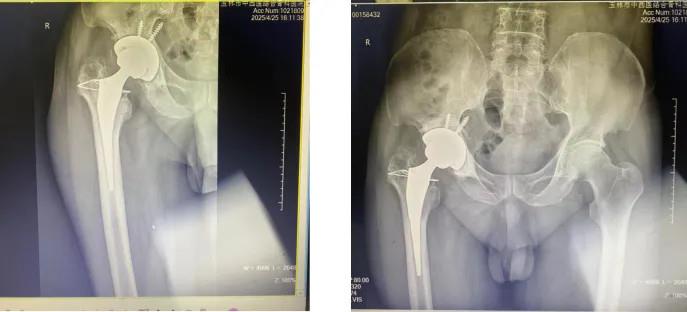

2024年初,覃大爷右髋部无明显诱因下突然出现疼痛,近一个月来病情急转直下 —— 夜间平躺超十分钟便会被痛醒,强效止痛药与安眠药相继失效。“只能靠着床头打盹,白天连端水杯的力气都没有。” 家属目睹老人日渐消瘦,焦虑万分。今年 4 月,患者辗转来到我院骨关节感染科,庞家省主任带领团队展开细致诊疗:右髋部疼痛如灼,关节活动度因疼痛近乎丧失,强迫体位,无法平卧,影像学检查显示右髋部周围组织呈弥漫性信号,结合既往结核病病史(未规范治理),右髋关节置换手术史,确诊为右髋关节置换术后结核性感染,同时假体已出现松动,多种因素共同影响造成覃大爷剧痛难忍。

(术前DR)